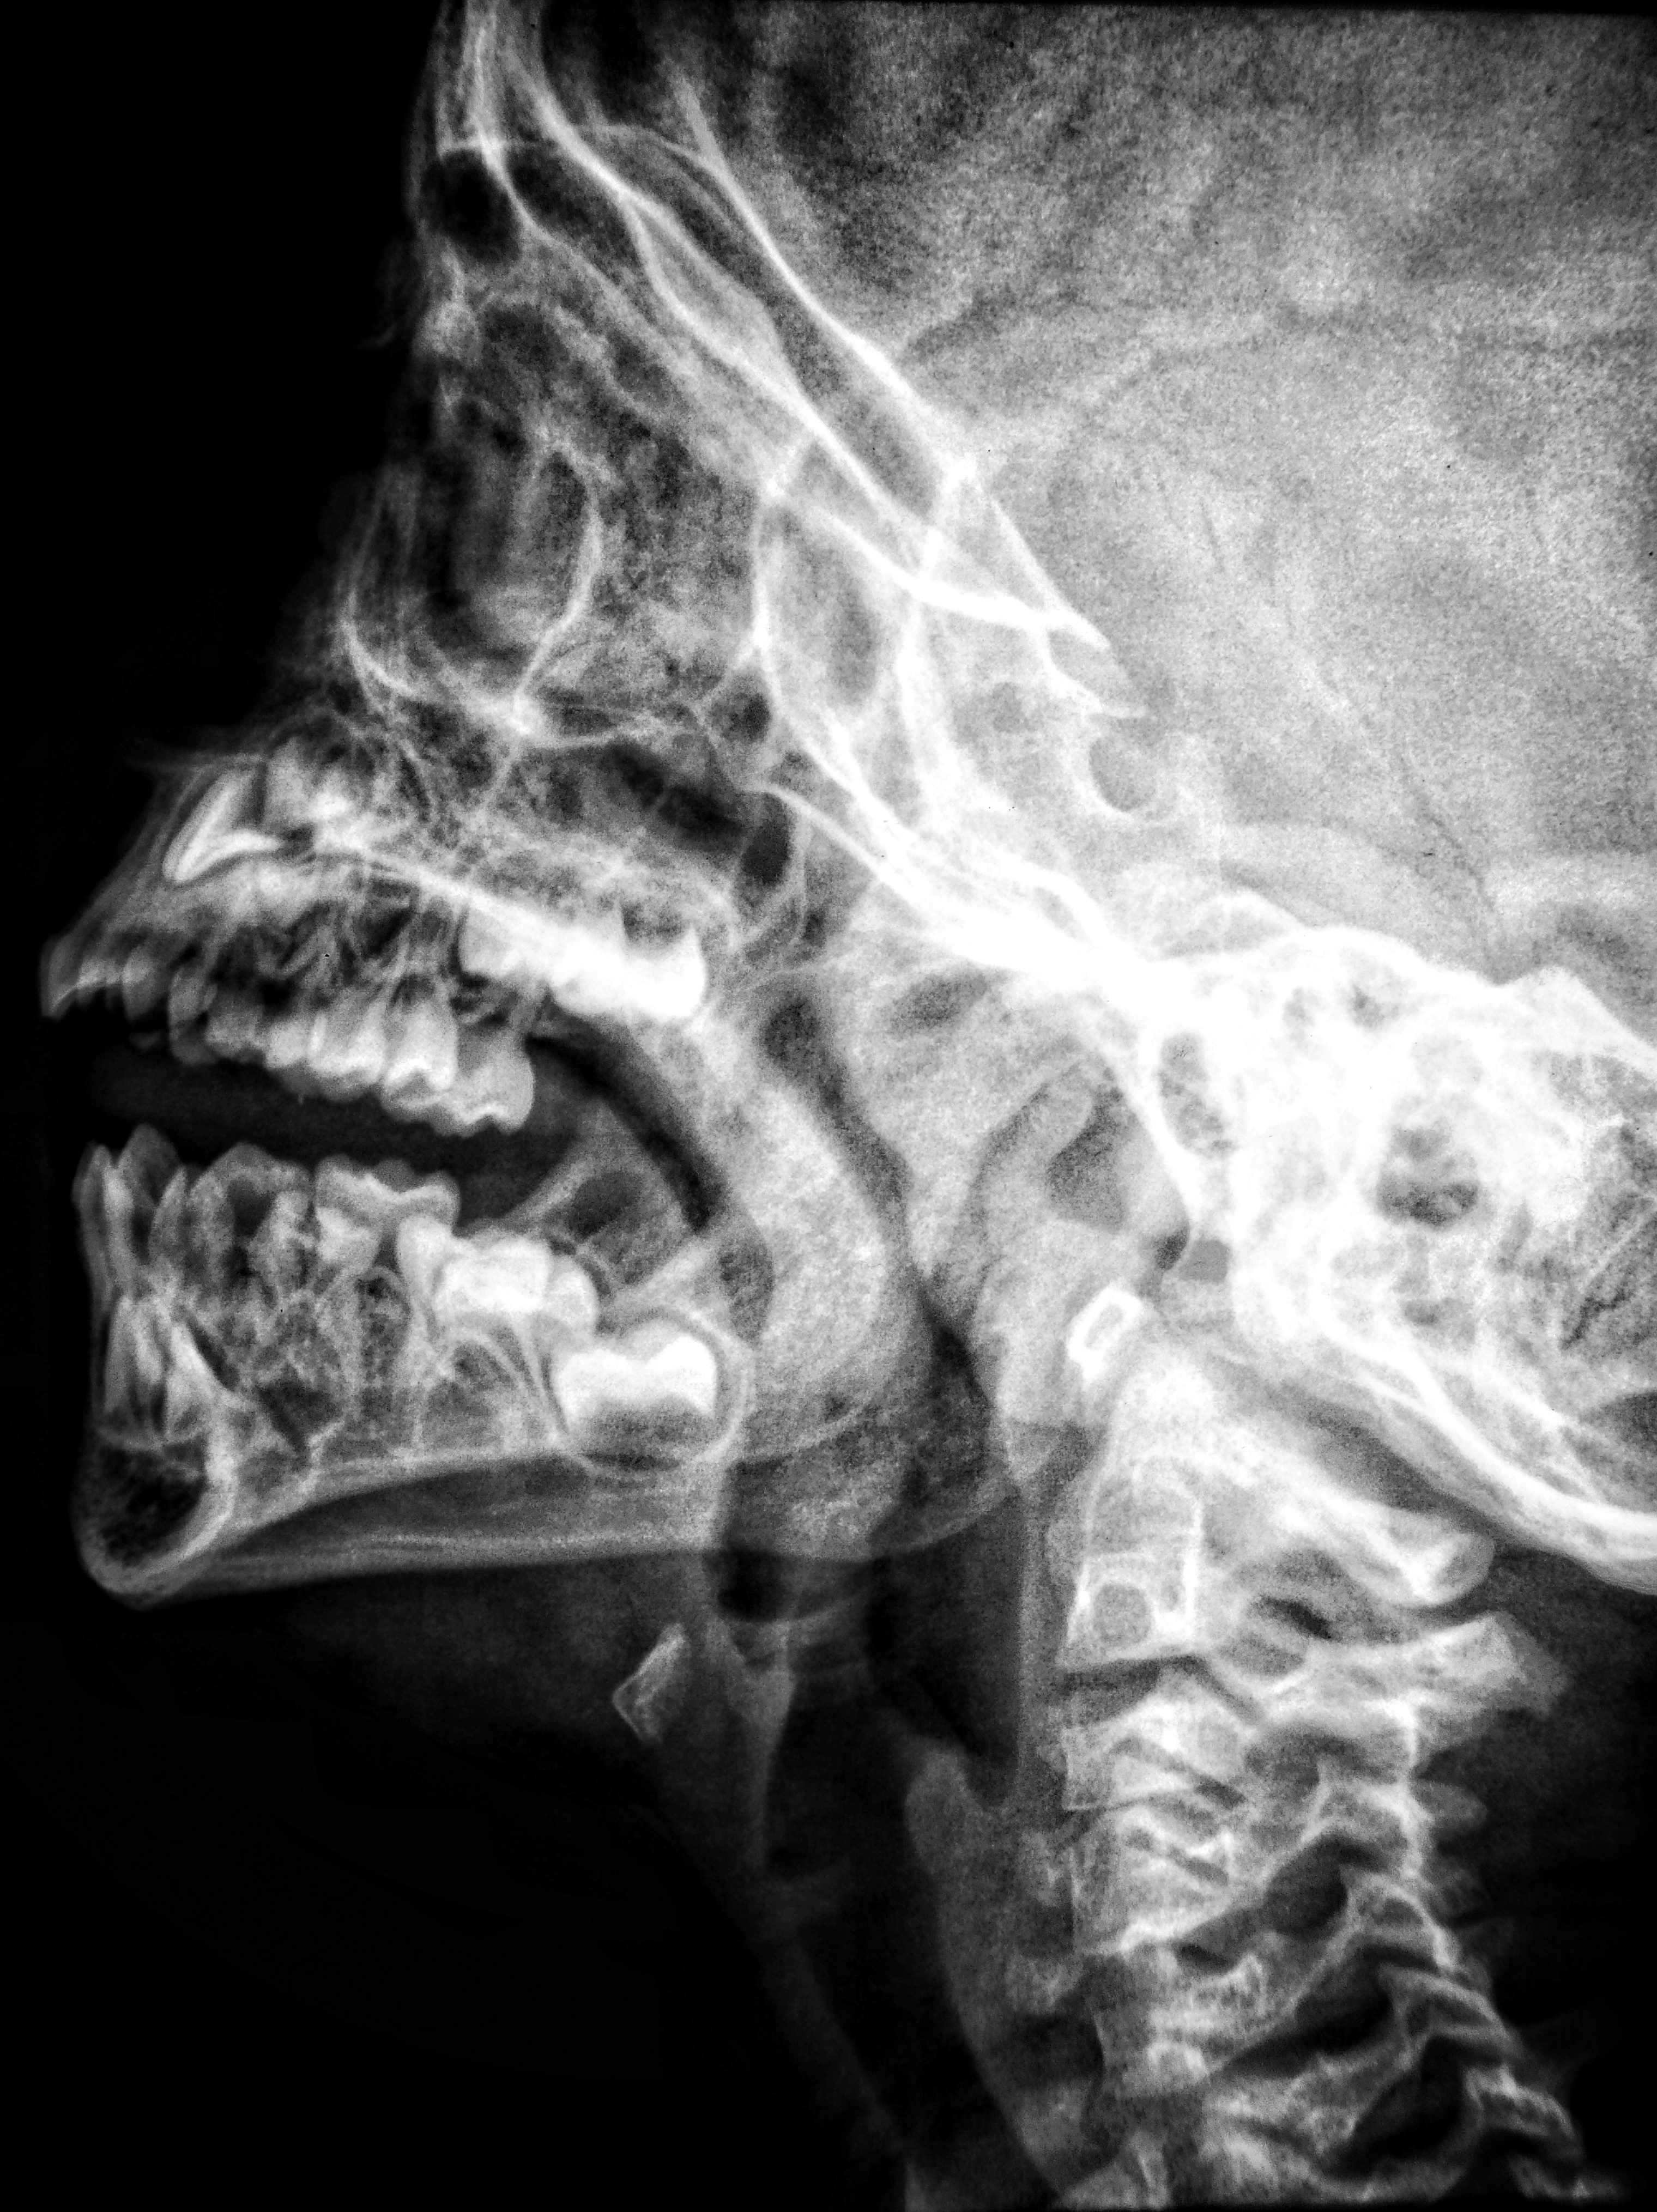

👂 Why A Second Opinion Always Matters

Or even a third, in this healthcare system.

I’m very reliant on the U.S. Healthcare system.

By that, I mean I trust that the doctors performing my physicals, cardiorespiratory tests…